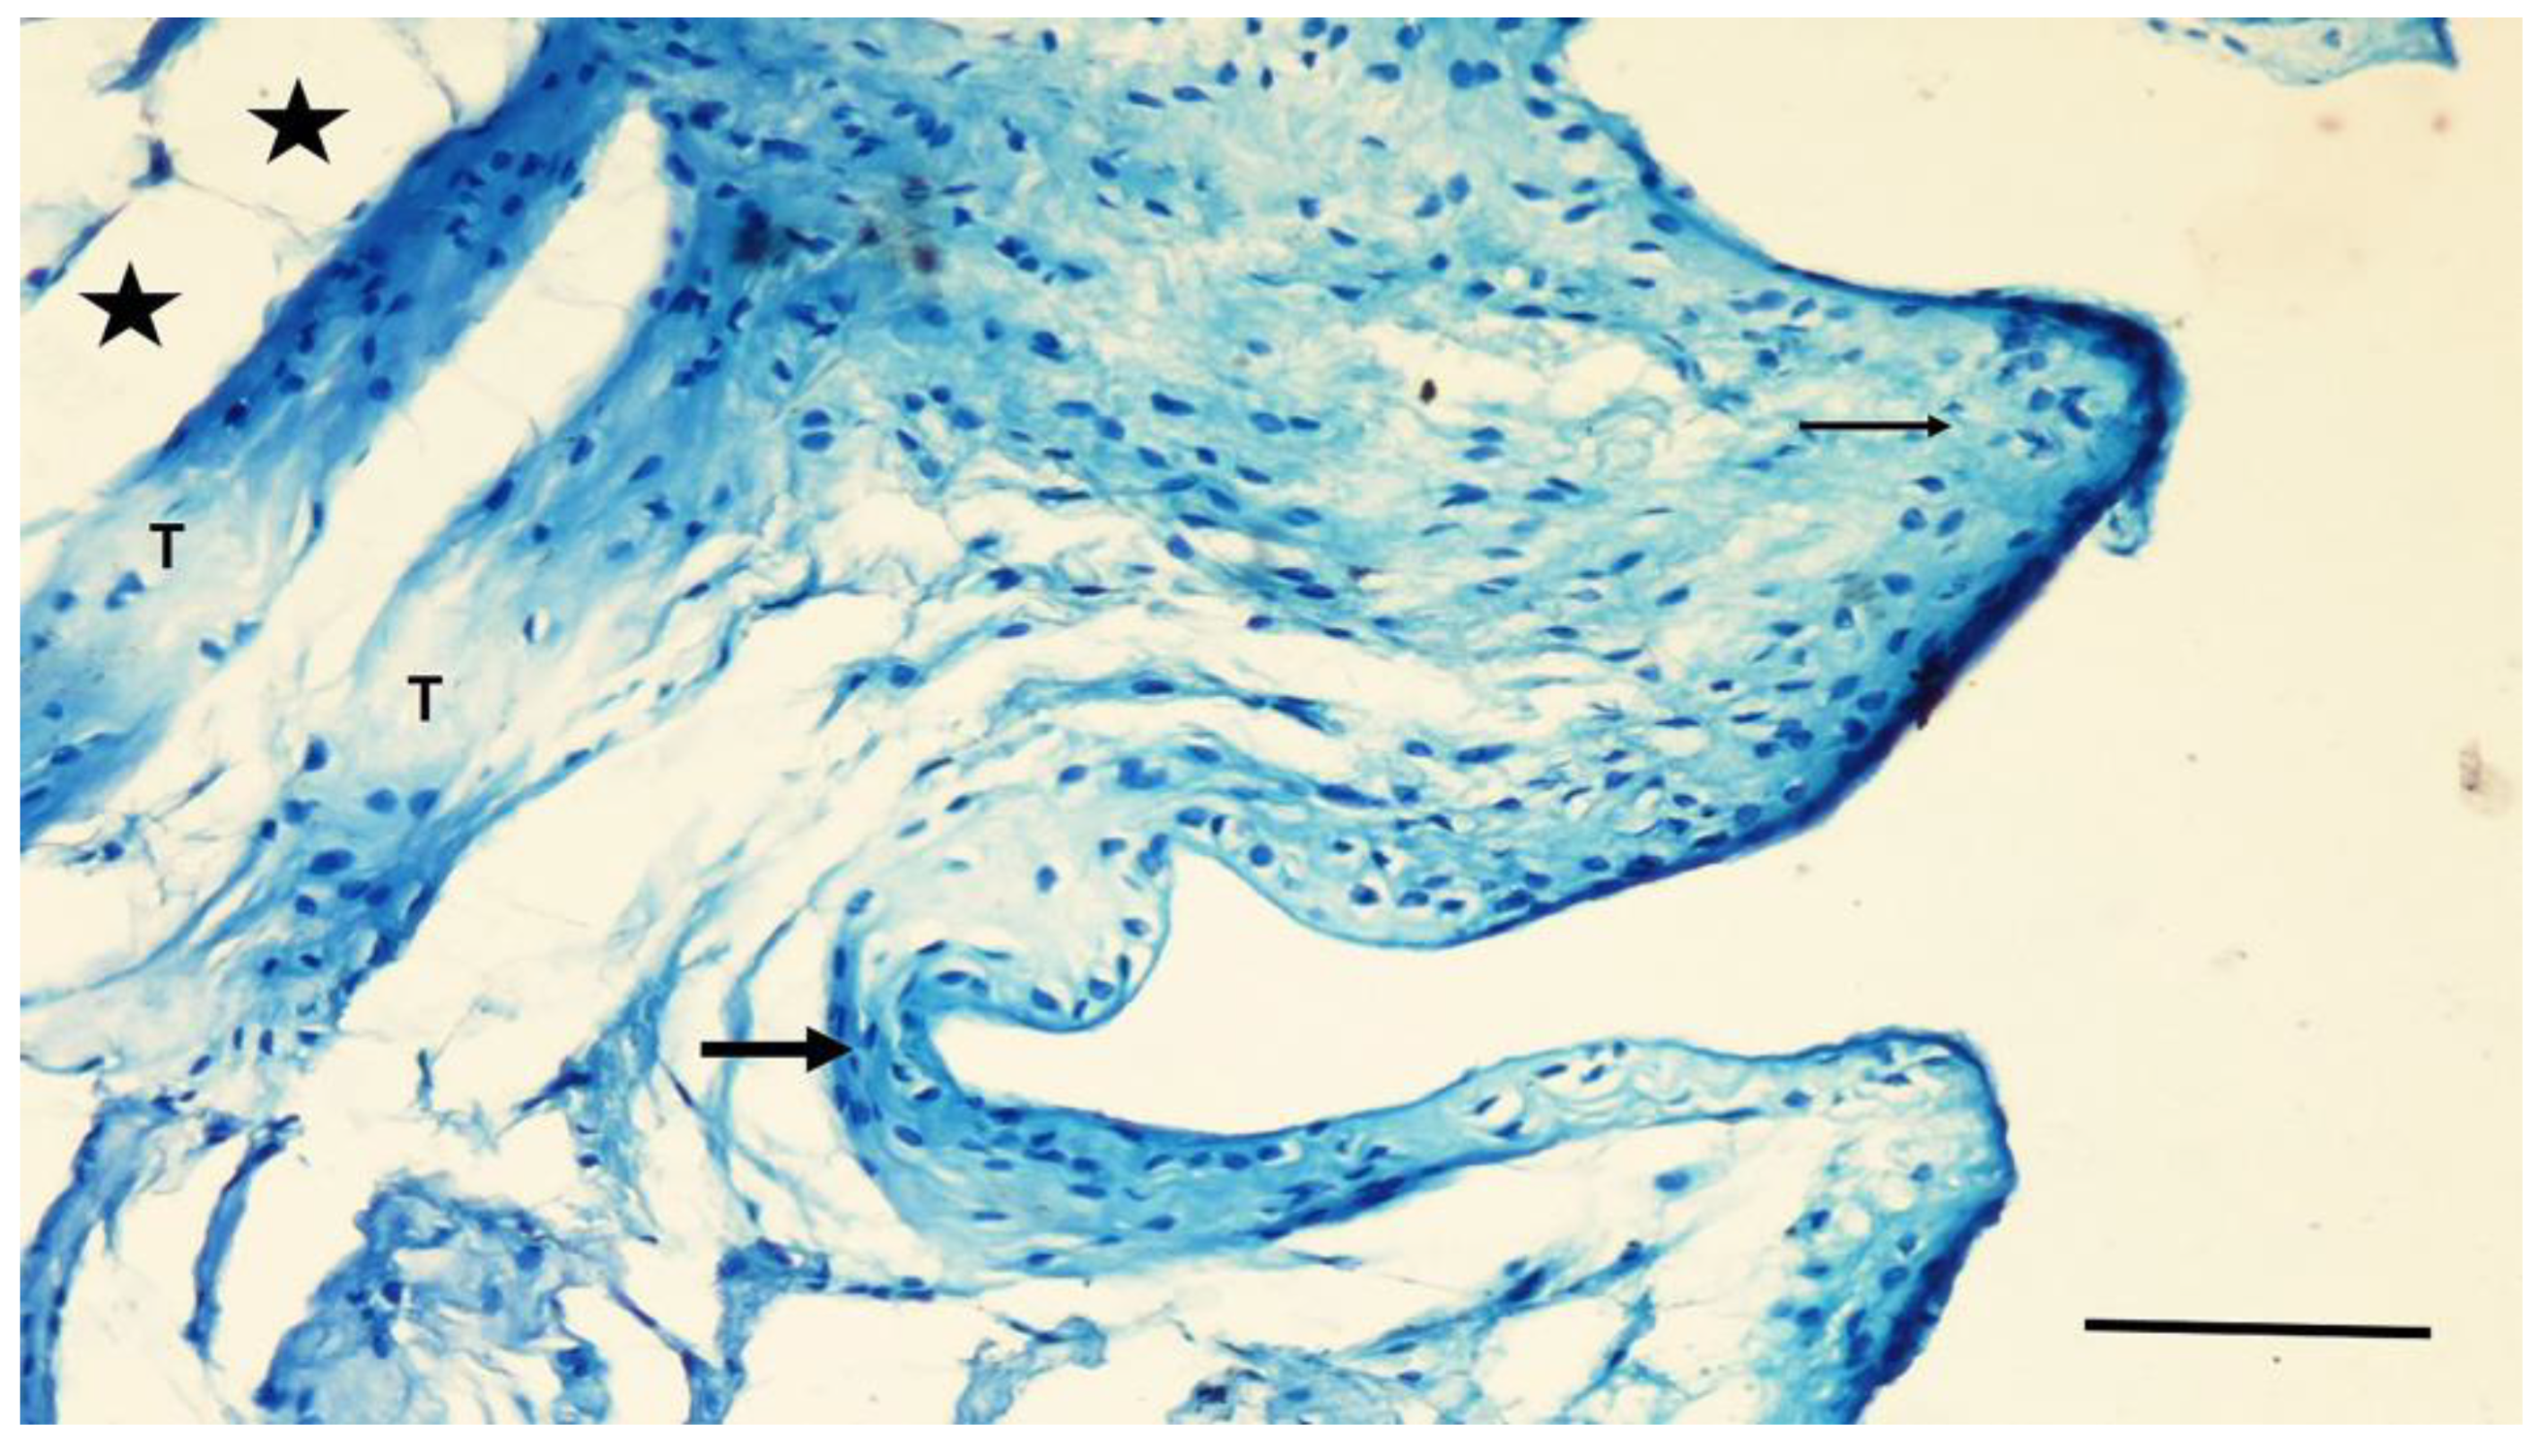

In the NC group, the grooves of the implant in the intercortical region were filled with a thin band of new bone tissue. Fibrocartilaginous tissue was found adjacent to the screw grooves and in the intergroove region (Figure 6). Thin bone trabeculae and myeloid tissue mainly occupied the medullary region associated with the defect site.

Figure 6.

A section from the NC group. Fibrocartilaginous tissue (arrow) covering the grooves and intergroove regions of the screw. Deeper regions are filled with trabecular bone (T) and adipocytes (asterisks). Toluidine blue staining. Magnification bar: 100 µm.